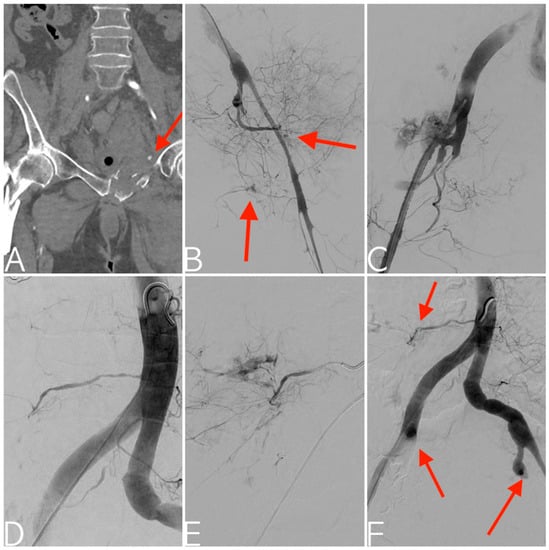

2.2. Treatment